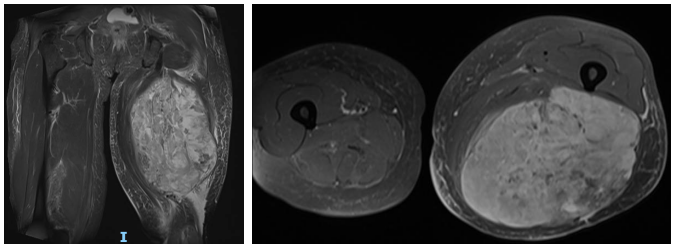

刘女士术前影像:巨大软组织肿瘤累及左侧大腿

辗转多院后,刘女士最终来到柳州市工人医院关节外科/骨肿瘤科,乐国平主任团队经过详细检查与病情分析,认为该肿物巨大,进展较快,恶性几率很大,通过增强CT及下肢CTA、增强MRI检查发现,肿瘤边界与下肢大血管神经束紧密粘连,而且滋养肿瘤的血管交通支丰富,手术切除损伤重要血管风险极大。完善相关检查后,又为患者行穿刺取病理活检,病理结果提示左侧大腿粘液性脂肪肉瘤。

考虑到刘女士年龄较高,肿瘤体积巨大,手术风险极大,经过肿瘤内科、医学影像科、麻醉科、病理科MDT多学科会诊,同时与患者及家属积极沟通后,乐国平主任团队决定为患者实施左大腿脂肪肉瘤广泛切除术。